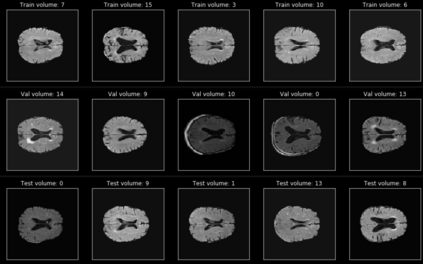

In recent years, data-driven machine learning (ML) methods have revolutionized the computer vision community by providing novel efficient solutions to many unsolved (medical) image analysis problems. However, due to the increasing privacy concerns and data fragmentation on many different sites, existing medical data are not fully utilized, thus limiting the potential of ML. Federated learning (FL) enables multiple parties to collaboratively train a ML model without exchanging local data. However, data heterogeneity (non-IID) among the distributed clients is yet a challenge. To this end, we propose a novel federated method, denoted Federated Disentanglement (FedDis), to disentangle the parameter space into shape and appearance, and only share the shape parameter with the clients. FedDis is based on the assumption that the anatomical structure in brain MRI images is similar across multiple institutions, and sharing the shape knowledge would be beneficial in anomaly detection. In this paper, we leverage healthy brain scans of 623 subjects from multiple sites with real data (OASIS, ADNI) in a privacy-preserving fashion to learn a model of normal anatomy, that allows to segment abnormal structures. We demonstrate a superior performance of FedDis on real pathological databases containing 109 subjects; two publicly available MS Lesions (MSLUB, MSISBI), and an in-house database with MS and Glioblastoma (MSI and GBI). FedDis achieved an average dice performance of 0.38, outperforming the state-of-the-art (SOTA) auto-encoder by 42% and the SOTA federated method by 11%. Further, we illustrate that FedDis learns a shape embedding that is orthogonal to the appearance and consistent under different intensity augmentations.